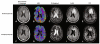

Fluid attenuated inversion recovery (FLAIR) MRI sequences have become an indispensible tool for defining the malignant boundary in patients with brain tumors by nulling the signal contribution from cerebrospinal fluid allowing both regions of edema and regions of non-enhancing, infiltrating tumor to become hyperintense on resulting images. In the current study we examined the utility of a three-dimensional double inversion recovery (DIR) sequence that additionally nulls the MR signal associated with white matter, implemented either pre-contrast or post-contrast, in order to determine whether this sequence allows for better differentiation between tumor and normal brain tissue. T1- and T2-weighted, FLAIR, dynamic susceptibility contrast (DSC)-MRI estimates of cerebral blood volume (rCBV), contrast-enhanced T1-weighted images (T1+C), and DIR data (pre- or post-contrast) were acquired in 22 patients with glioblastoma. Contrast-to-noise (CNR) and tumor volumes were compared between DIR and FLAIR sequences. Line profiles across regions of tumor were generated to evaluate similarities between image contrasts. Additionally, voxel-wise associations between DIR and other sequences were examined. Results suggested post-contrast DIR images were hyperintense (bright) in regions spatially similar those having FLAIR hyperintensity and hypointense (dark) in regions with contrast-enhancement or elevated rCBV due to the high sensitivity of 3D turbo spin echo sequences to susceptibility differences between different tissues. DIR tumor volumes were statistically smaller than tumor volumes as defined by FLAIR (Paired t test, P = 0.0084), averaging a difference of approximately 14 mL or 24 %. DIR images had approximately 1.5× higher lesion CNR compared with FLAIR images (Paired t test, P = 0.0048). Line profiles across tumor regions and scatter plots of voxel-wise coherence between different contrasts confirmed a positive correlation between DIR and FLAIR signal intensity and a negative correlation between DIR and both post-contrast T1-weighted image signal intensity and rCBV. Additional discrepancies between FLAIR and DIR abnormal regions were also observed, together suggesting DIR may provide additional information beyond that of FLAIR.